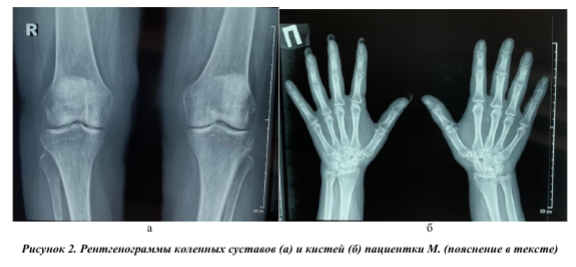

По данным рентгенографии коленных суставов выявлен двусторонний гонартроз II стадии, кистей - рентгенологические признаки артрита II стадии (Рис.2). На рентгенограмме стоп определялся выраженный остеопороз, суставные щели обоих плюсне-фаланговых сочленений равномерно сужены, уплотнены суставные поверхности, в проекции головок плюсневых костей - пробойники, что характерно для подагрического артрита слева II стадии, справа III-IV стадии (Рис.3).

По данным авторов, умеренные рентгенологические изменения суставов возникают в среднем через 9 лет, а более значительные через 10-15 лет и более [5]. У наблюдаемой нами пациентки рентгенологические изменения были выявлены уже через 5 лет от начала заболевания.